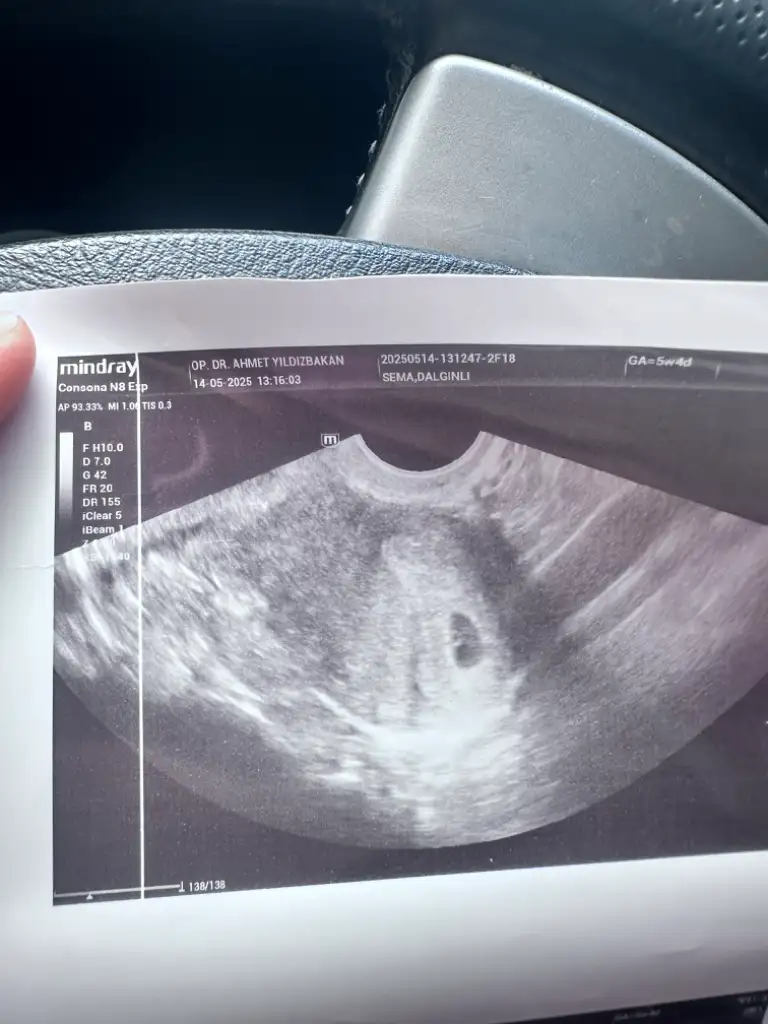

Kızlar keseme bakar mısınız normal mi 5+2 bugün doktor dedi bebek var içinde 10 gün sonra kalp atışına çağirdi